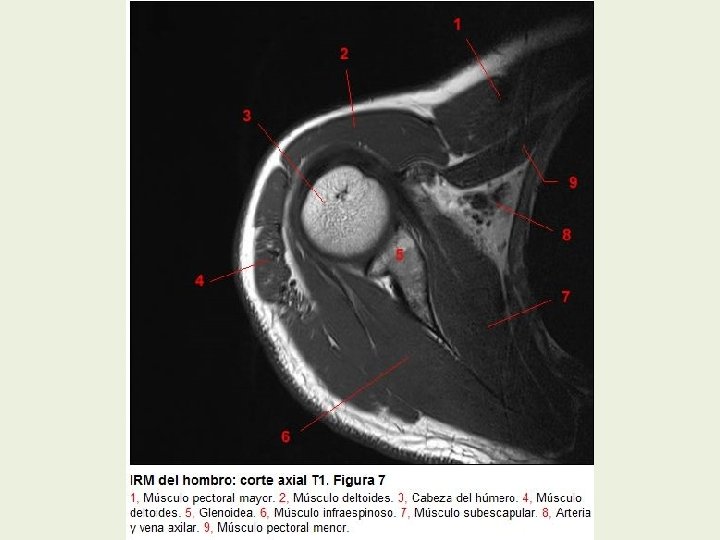

Hombro Cortes axiales RMN